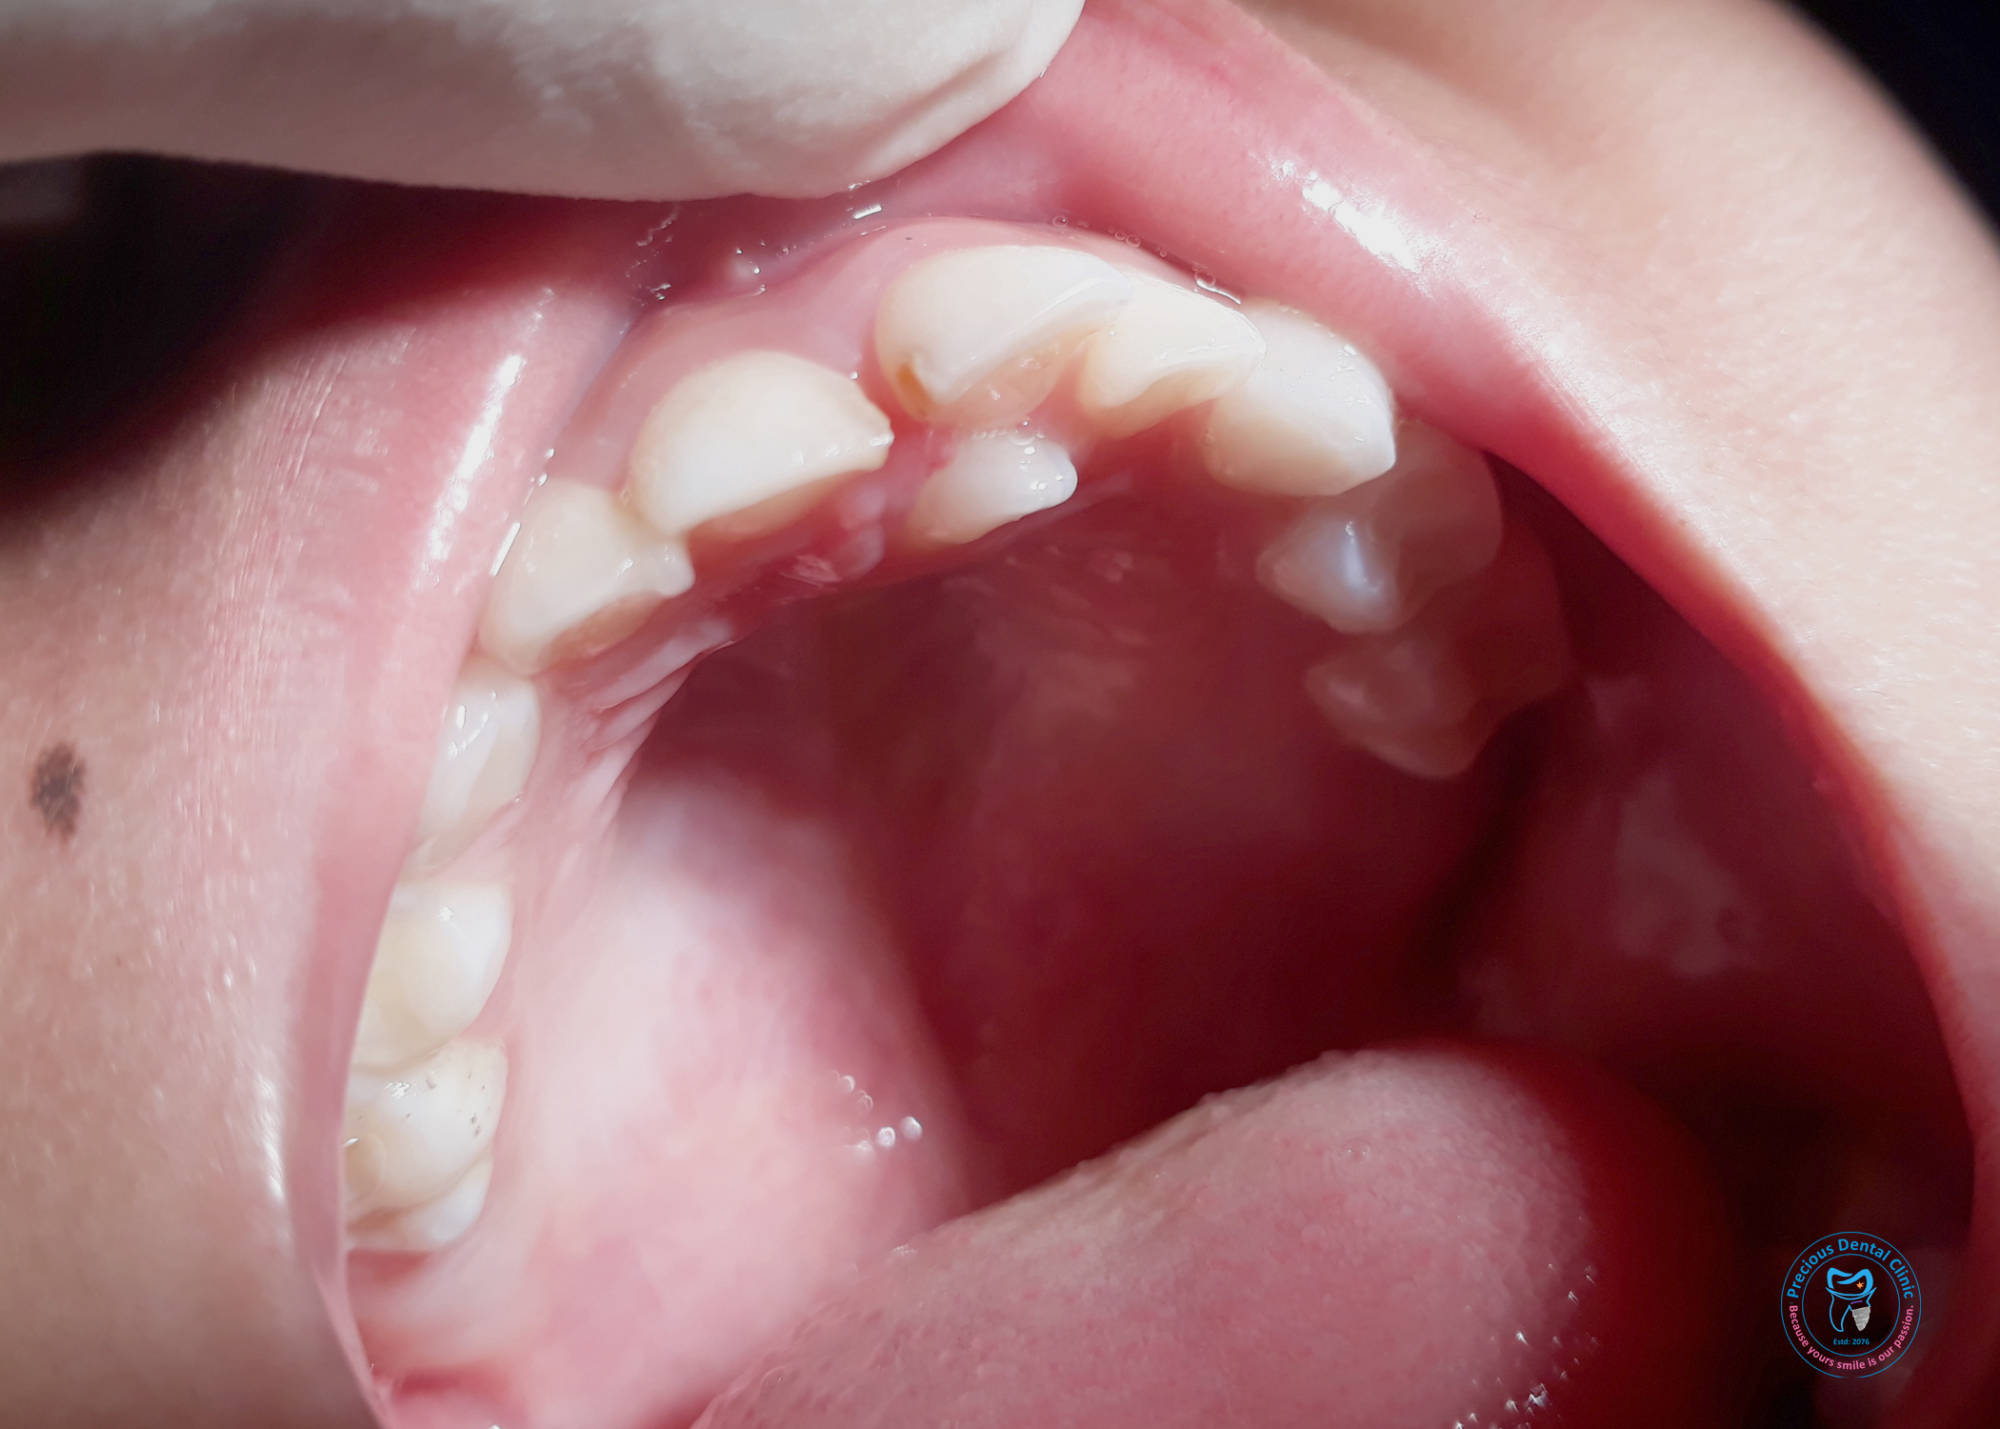

Collection of photos, here you will find the photos of doctor, services, environment and work.